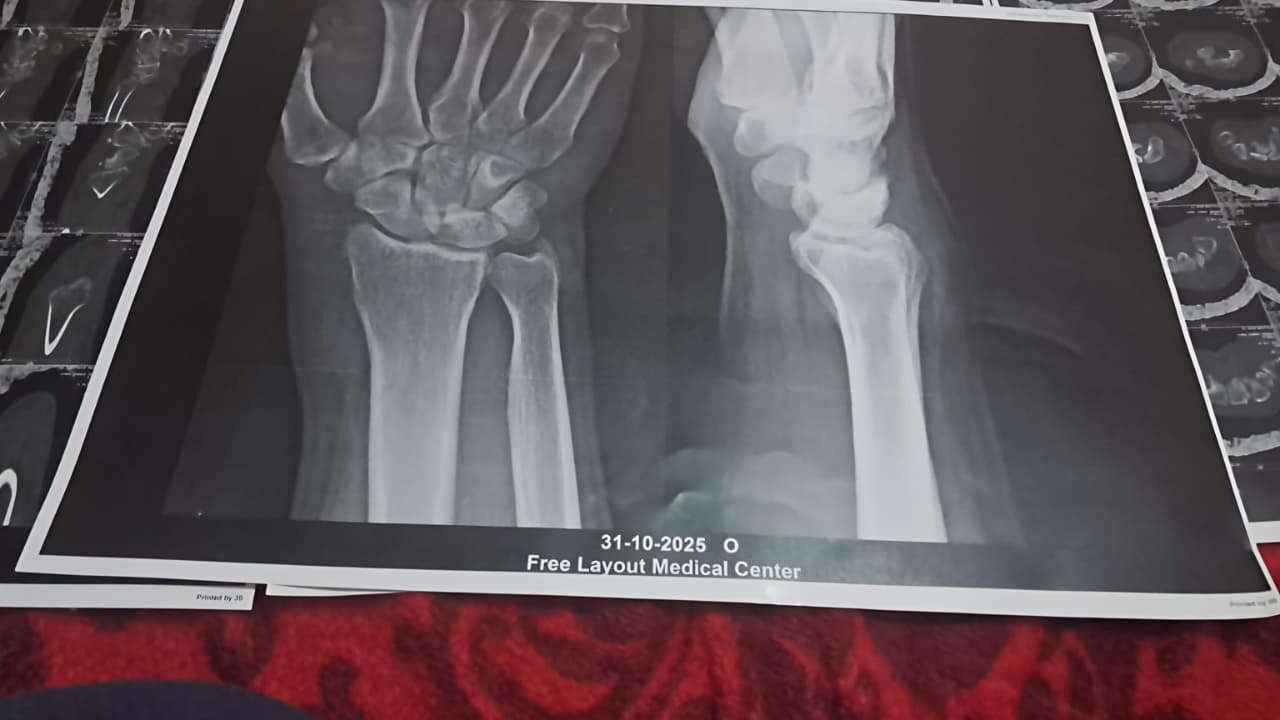

أما أحمد (اسم مستعار) 43 عامًا، فقضى 15 عامًا في العمل داخل الشركة، يتقاضى خلالها راتبًا 3400 جنيه، قبل أن تتغيّر حياته المهنية فجأة بعد إصابته بشرخ في مفصل اليد أثناء العمل.

يحكي أحمد أن إدارة الشركة منحته إجازة مرضية قانونية، لكنه عندما طلب مدها لحين اكتمال تعافيه، فوجئ بقرار وقفه عن العمل. وهنا يقول: "روحت لمدير الأمن أشرح له حالتي، فقال لي: دا مايجيش ومايدخلش تاني".